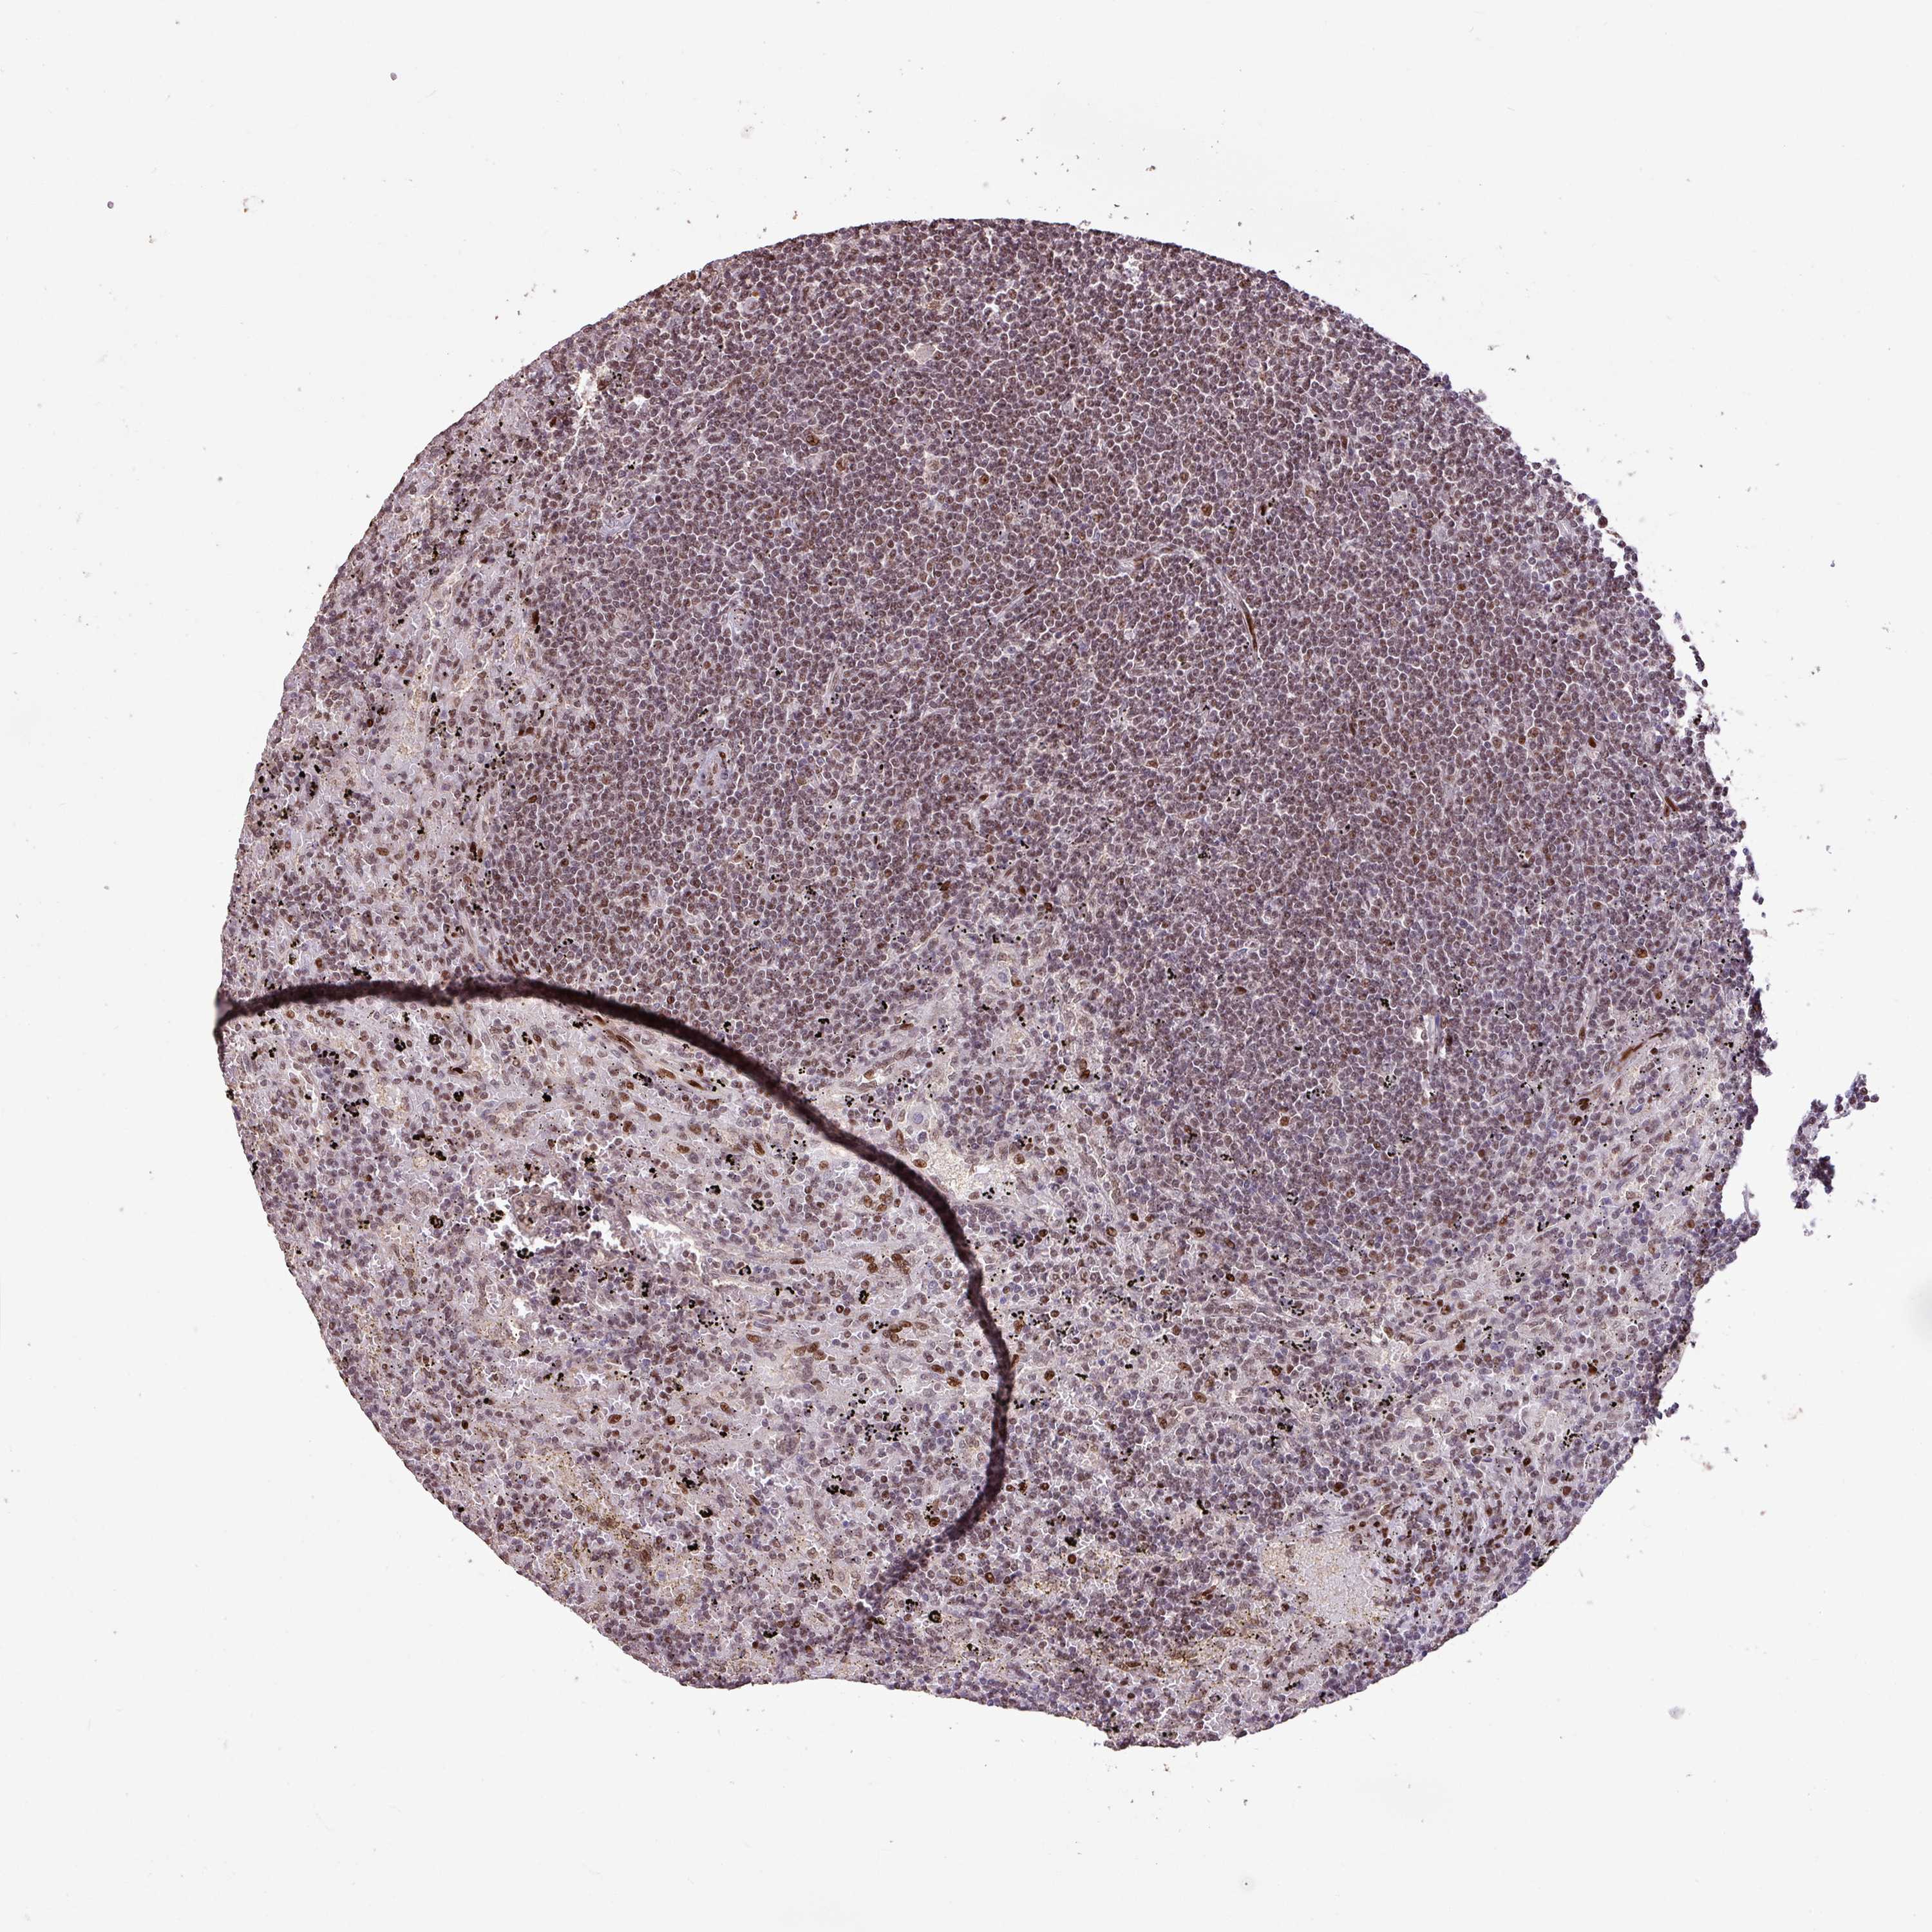

LYMPHOMA - Protein expressioni

A mouse-over function shows sample information and annotation data. Click on an image to view it in a full screen mode. Samples can be filtered based on level of antibody staining by selecting one or several of the following categories: high, medium, low and not detected. The assay and annotation is described here.

Antibody stainingi

Antibody staining in the annotated cell types in the current human tissue is reported as not detected, low, medium, or high, based on conventional immunohistochemistry profiling in selected tissues. This score is based on the combination of the staining intensity and fraction of stained cells.

Each image is clickable and will lead to virtual microscopy that enables deeper exploration of all samples and also displays staining intensity scores, fraction scores and subcellular localization as well as patient and tissue information for each sample.

Antibody HPA053153

Staining

Medium

Intensity

Weak

Quantity

<25%

Location

Nuclear

Hodgkin's disease, NOS

Malignant lymphoma, non-Hodgkin's type, High grade

Malignant lymphoma, non-Hodgkin's type, Low grade